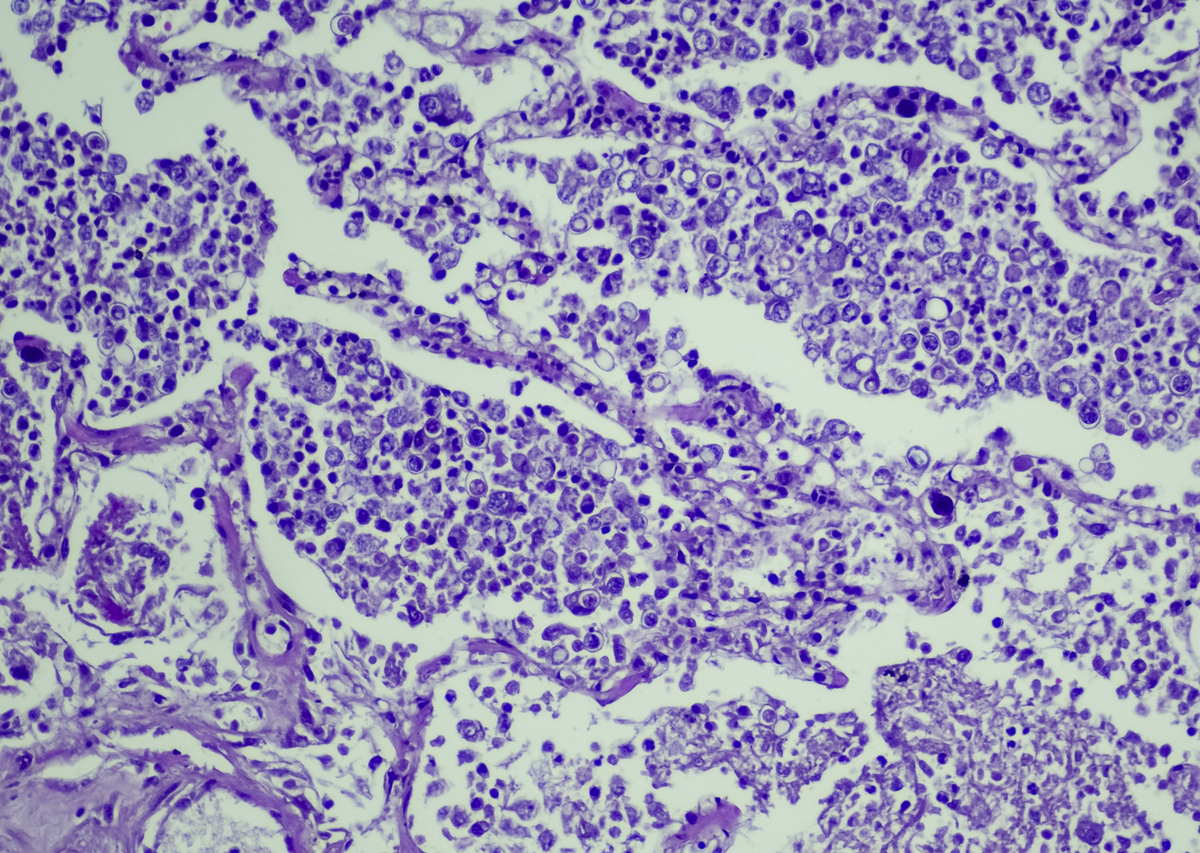

原文: CEUS confirmed the unenhanced floating thrombus at the distal end of the plaque,which was confirmed by CTA and DSA. Additionally, CEUS also revealed small ulcers and abundant neovascularization within the plaque that were not visible on routine ultrasound.